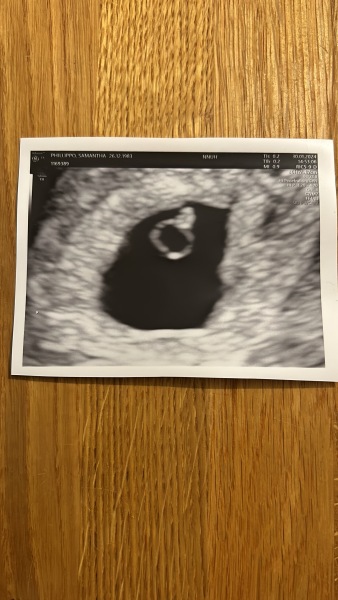

I had a private scan last week they also said similar they thought I was more around 5weeks rather than 6. Said come back in 2weeks but I think I'm going to hold off and wait to see my midwife on the 24th. I'll attach a photo. Wasn't much to see at all but was told this can be very normal. Pregnancy also in left womb this time.

4-5weeks pregnant